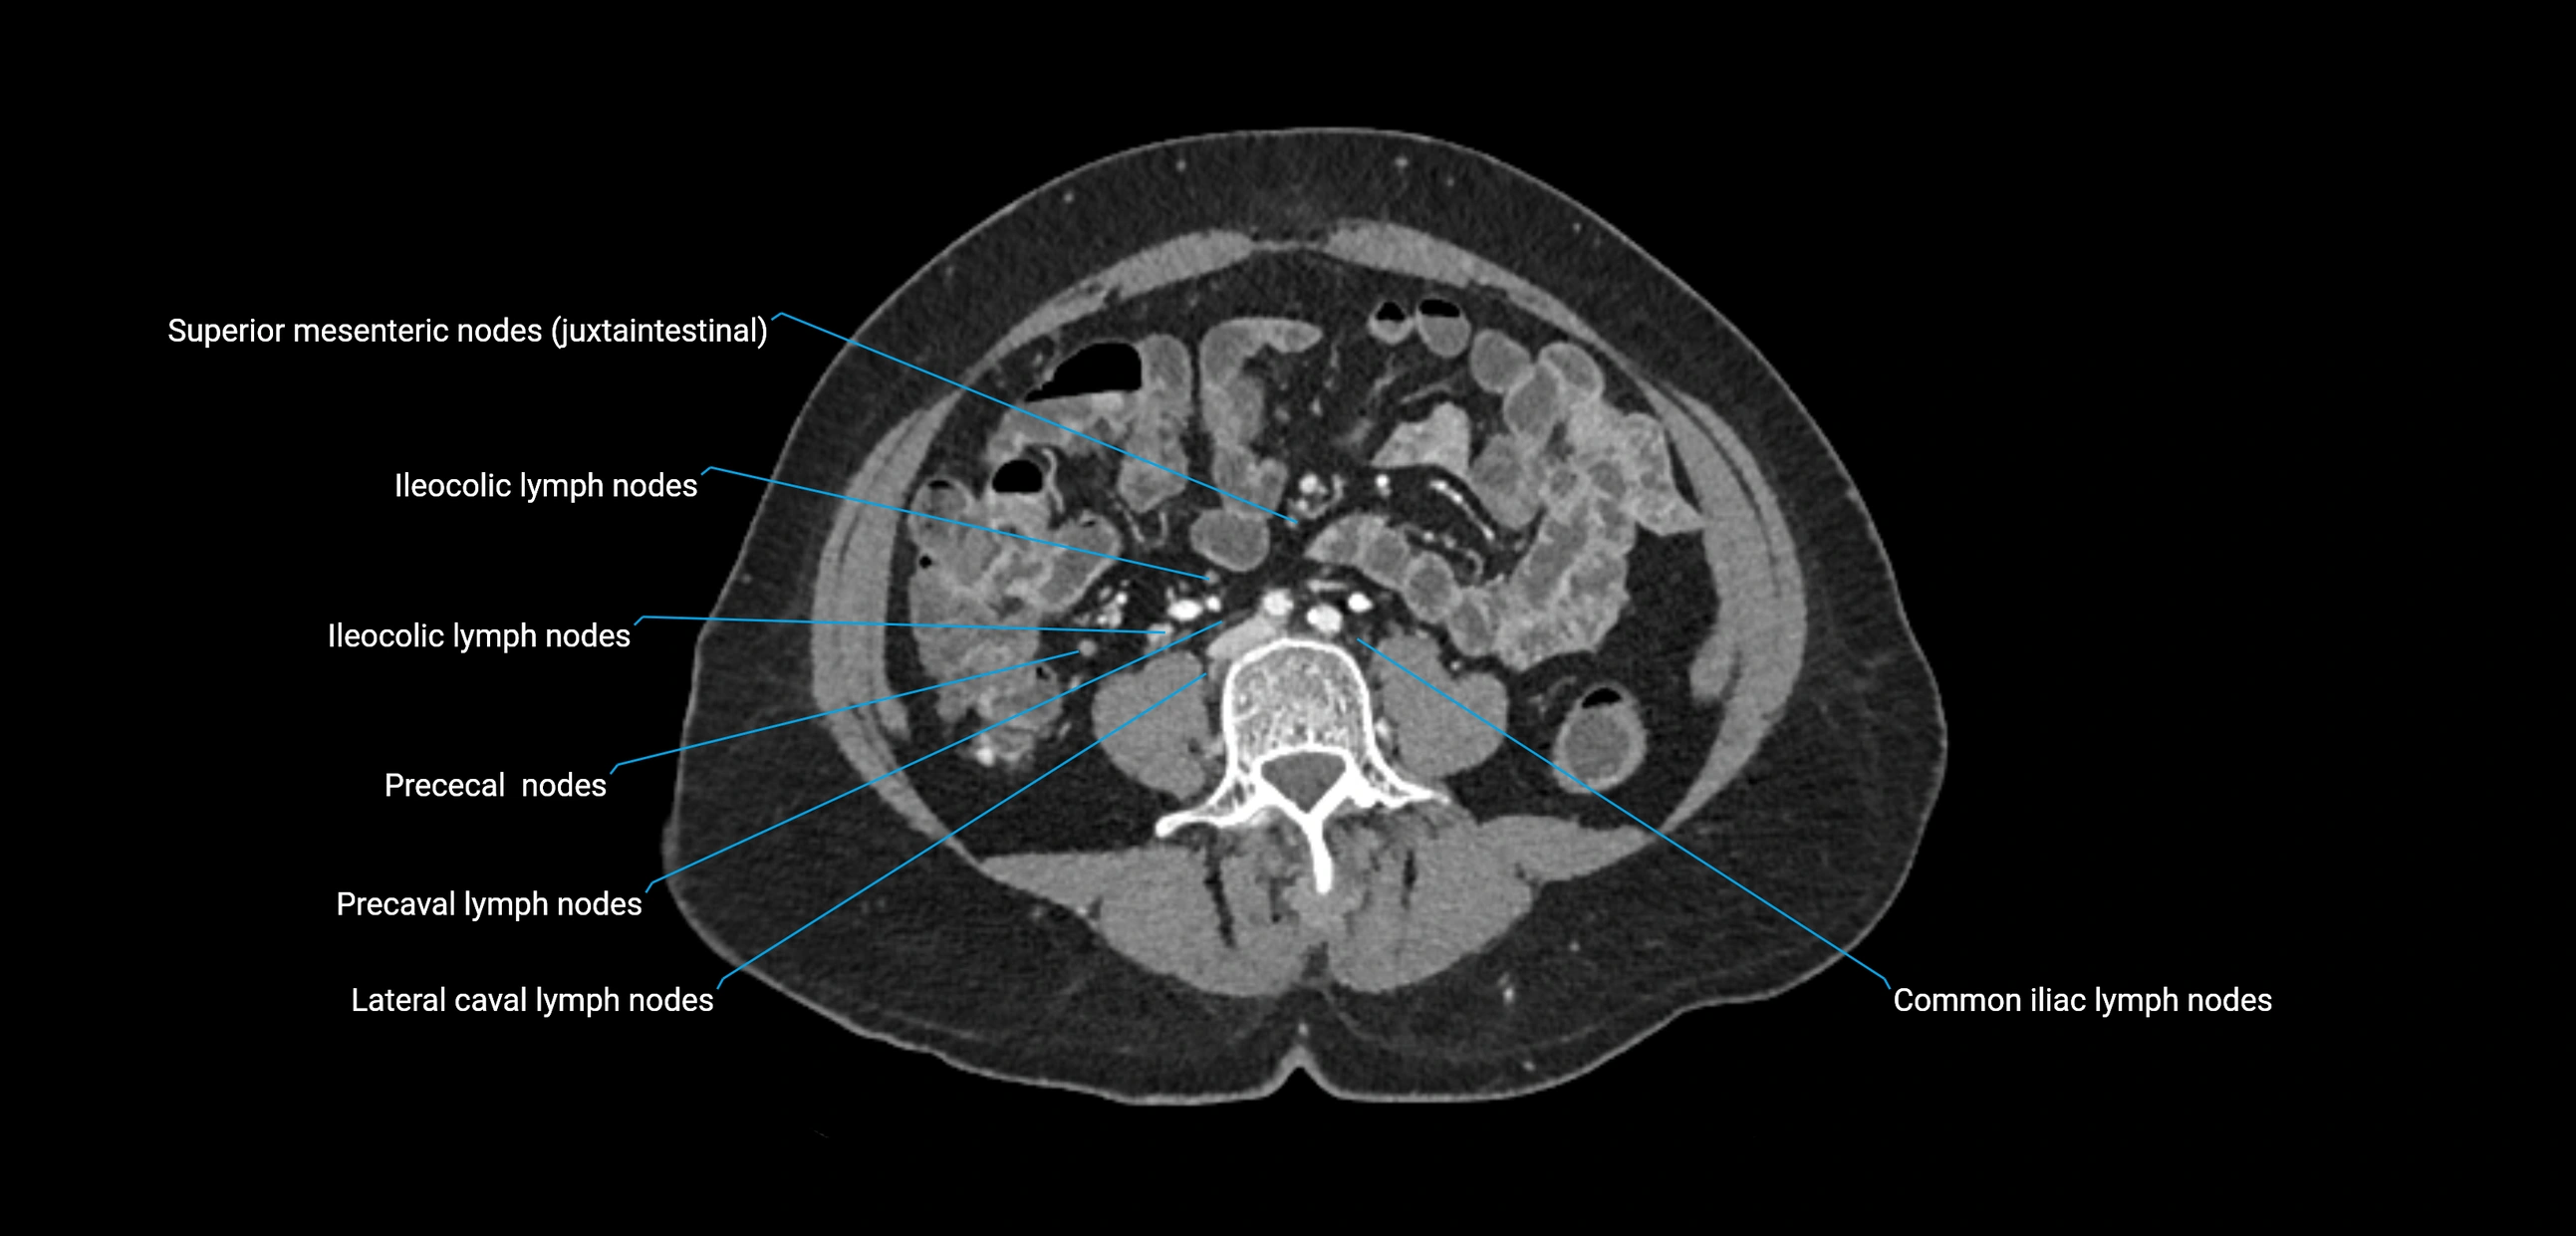

CT Appearance

CT Pre-Contrast:

• Nodes appear as soft-tissue density nodules adjacent to the aorta and IVC

• Calcification may be seen in chronic infections (e.g., tuberculosis)

CT Post-Contrast:

• Normal nodes enhance homogeneously

• Malignant nodes may show heterogeneous enhancement, central necrosis, or conglomerate formation

• Size >1 cm short axis is suspicious, though morphology and distribution are equally important

CT image

image